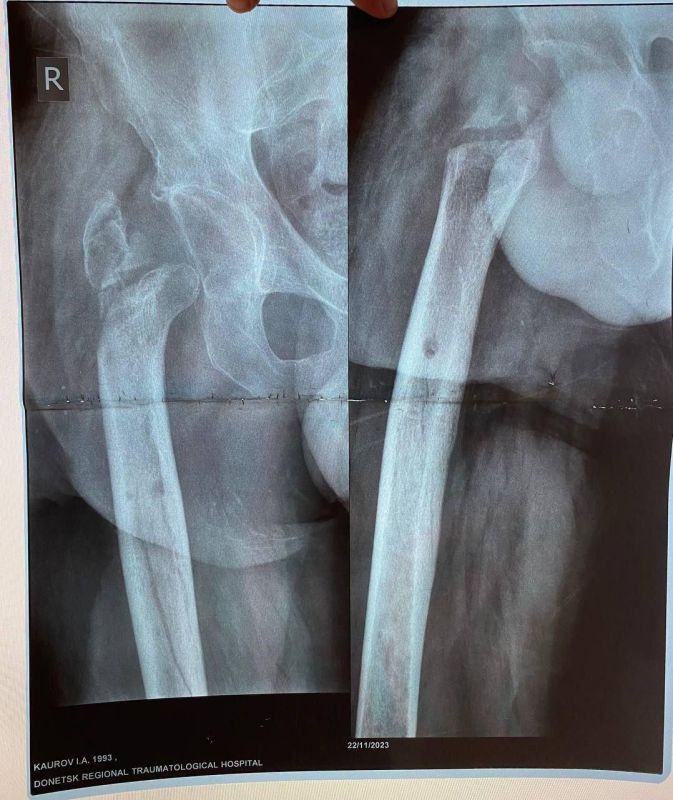

Об этом сообщила министр здравоохранения ЛНР Наталия Пащенко.Руководитель Минздрава рассказала, что борьба сержанта из ЛНР, мужчины 1993 года рождения, длилась три с половиной года. За это время он проходил лечение в десяти госпиталях, в том числе в...

Уникальная операция в Луганской республиканской клинической больнице вернула ветерану специальной военной операции (СВО) возможность ходить без хромоты. Об этом сообщила министр здравоохранения ЛНР Наталия Пащенко. Руководитель Минздрава...

Об этом сообщила министр здравоохранения ЛНР Наталия Пащенко в своем телеграм-канале.Боец ушел на фронт 25 февраля 2022 года, прошел через горнило Херсонщины, а тяжелое ранение получил 28 августа.«Из-за обширных повреждений и многократных операций...

Об этом сообщила министр здравоохранения ЛНР Наталия Пащенко.Боец ушел на фронт 25 февраля 2022 года, прошел через горнило Херсонщины, а тяжелое ранение получил 28 августа.«Три с половиной года борьбы. Десять госпиталей. И одна операция, которая...

Уникальная операция в Луганской РКБ вернула ветерану СВО возможность ходить без хромотыТри с половиной года борьбы. Десять госпиталей. И одна операция, которая изменила всё.История сержанта из ЛНР, 1993 года рождения — это не просто медицинский отчёт....